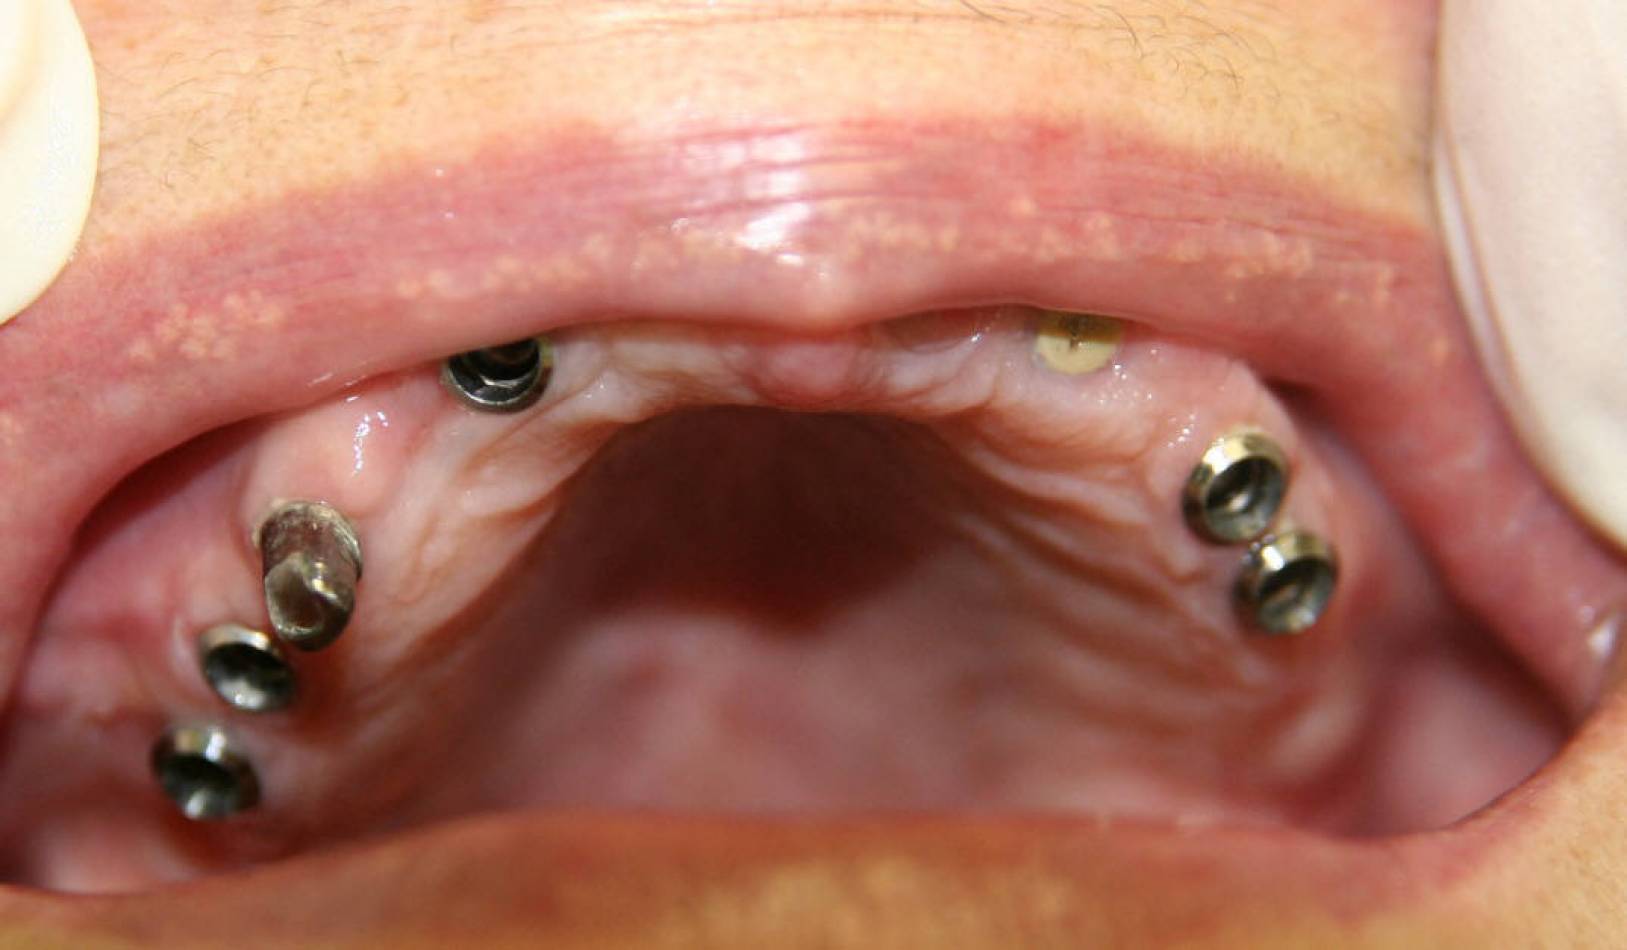

Si effettua implantologia con impianti STRAUMANN e tecnologia IDI EVOLUTION.